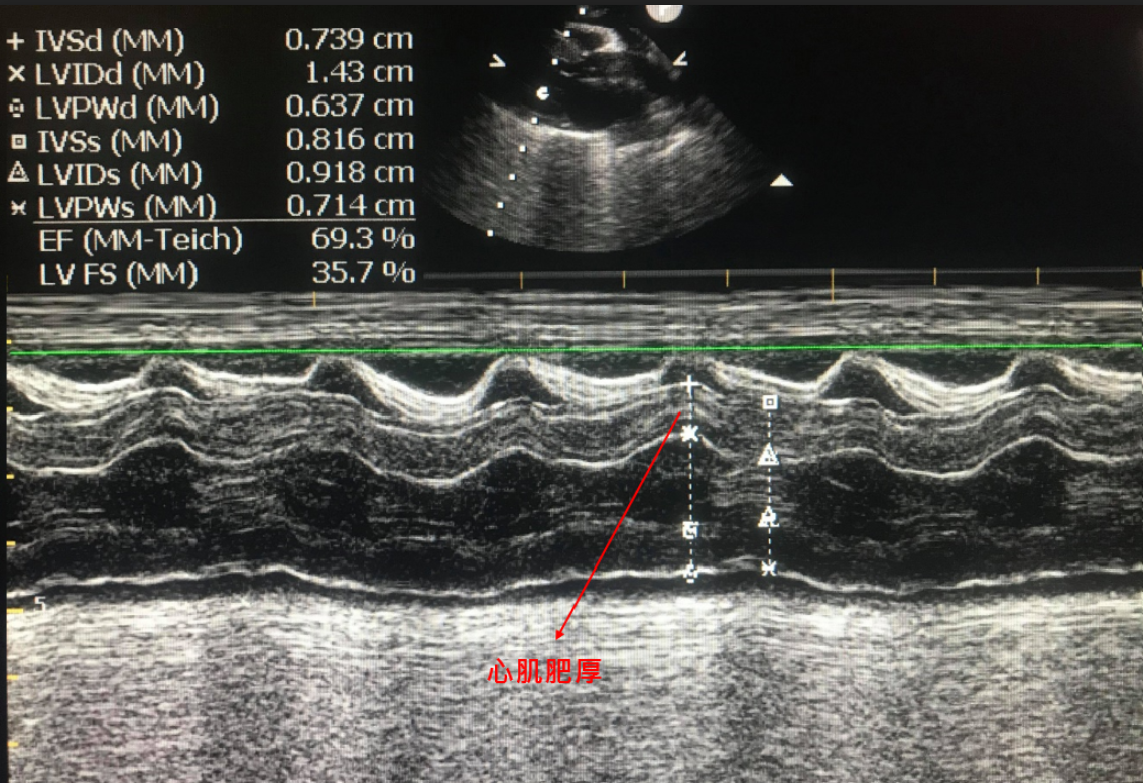

心臟快速掃描結果

左心室壁明顯肥厚

以下病例為10歲已絕育米克斯公貓,主人希望安排麻醉洗牙,術前健康檢查中發現貓咪已有嚴重心臟病,但主人平常並沒有發現任何異常。

及時發現心臟病,重新評估手術的必要性,調整麻醉及術後照護計畫可以避免事後的遺憾!